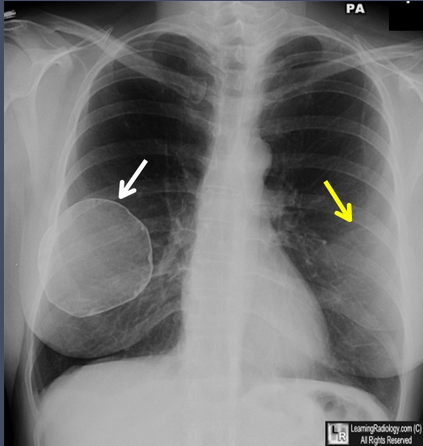

51岁女性乳房切除术前研究

胸部X光片(正位)

乳腺假体钙化。很薄的钙化曲线围绕在该患者12年前植入的右侧乳腺盐水假体囊周围(白色箭头)。左侧假体比正常乳腺组织密度较高(黄色箭头),但是在该胸片上未见到它的钙化。